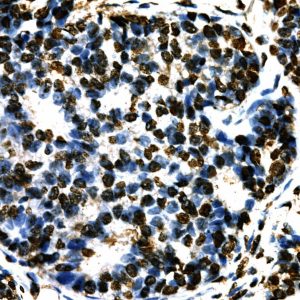

The fluoresceinated Hsa-miR-365A-3P probe has been designed from mature human miR-365A-3P sequence. This Hsa-miR-365A-3P identifies miR-365A-3P sequences in formalin-fixed, paraffin-embedded human tissues and freshly prepared frozen tissues by in situ hybridization. This probe does not react with normal human mRNA or nuclear DNA present in tissues.